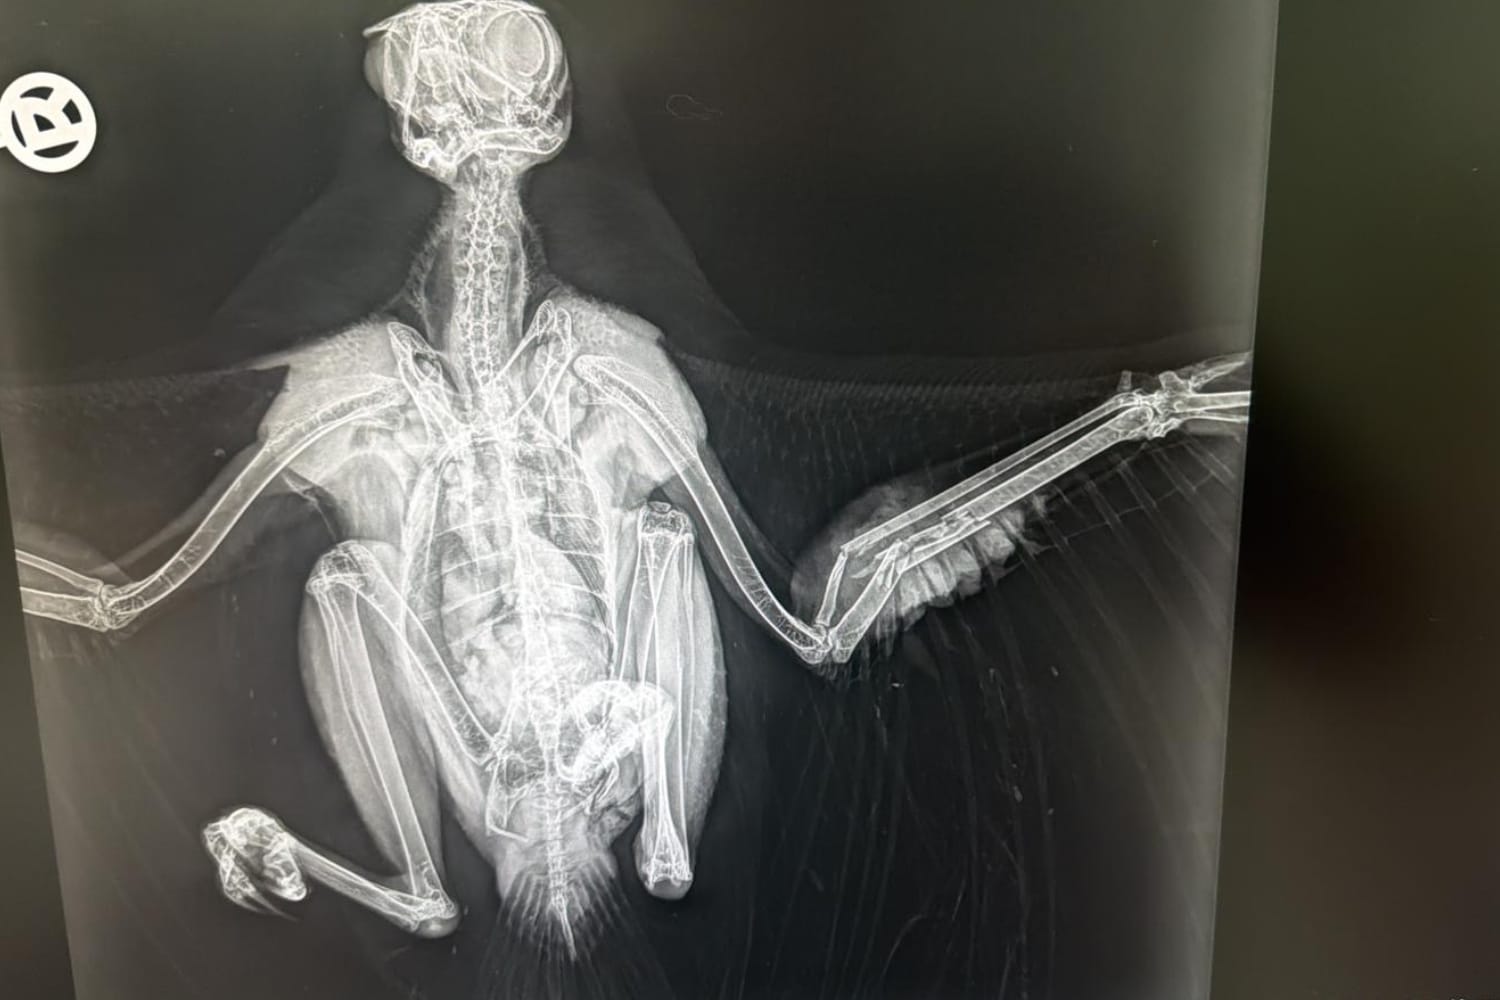

Knochen- und Gelenkchirurgie

Unser Spezialgebiet ist die Knochen- und Gelenkchirurgie. Bitte informieren Sie sich direkt vor Ort. Gerne vereinbaren wir mit Ihnen einen Termin.

Weichteil- und Knochenchirurgie